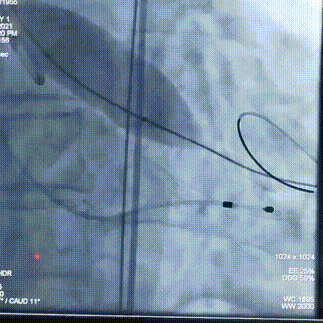

术中操作

球囊预扩

瓣膜初始定位

即刻超声评估示瓣周漏显著降低

瓣膜定位

经评估后植入左主干烟囱支架